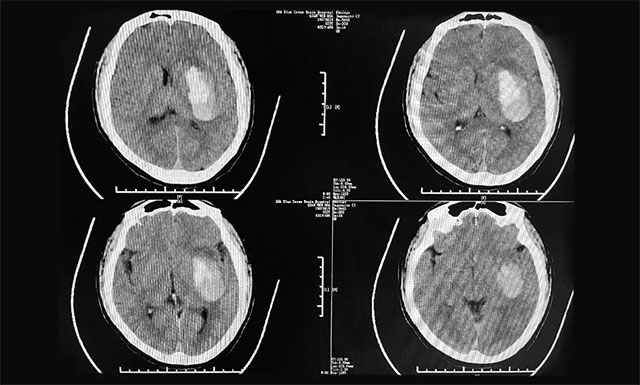

▲ 患者突发脑出血,致使其右侧偏瘫并昏迷不醒

在医院,小文紧急进行了头部CT检查,影像提示:左侧基底节区脑出血,当时小文人已经陷入昏迷,右侧肢体偏瘫,手术风险大,医院建议保守治疗并及时予以对症药物治疗。但鉴于丈夫小文病情危重,家人心急如焚,妻子林女士与家人商量后,决定转院进一步手术治疗,随后于当天下午,慕名转诊于上海蓝十字脑科医院,收治于神经外科6B病区。

对于小文当日入院情形,潘仁龙主任仍记忆犹新:“小文属于急性脑出血,当天下午4:30就转入了蓝十字脑科医院,为了方便治疗和及时手术,直接走医院脑卒中绿色通道。他来院时神志模糊,自动睁眼,无言语,其右侧偏瘫严重,上下肢肢体肌力仅有1级,情况危急,结合其头部影像检查,其出血约为40ml左右,需及早手术。”